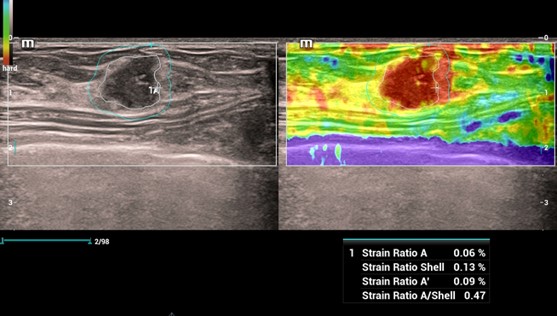

Strain Elastography - Natural Touch Elastografia

Natural Touch Elastografia, Strain Elastografia

Natural Touch Elastography

Natural Touch Elastography

Strain Elastography - Natural Touch Elastografia